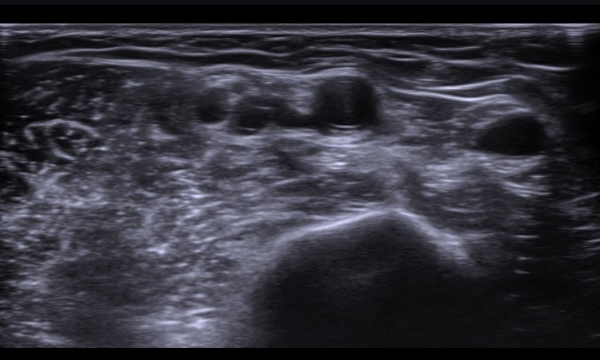

¼â°ñ¾Æ·¡¿¡¼­ »ó¿Ï½Å°æÃÑ Á¾´Ü¸é°Ë»ç¿¡¼­ »ó¿Ï½Å°æÃÑ ¿ÜÃø ²ö(lateral cord)ÀÇ Àú¿¡ÄÚ ºÎÁ¾ÀÌ

°üÂûµÈ´Ù(»çÁø 7).